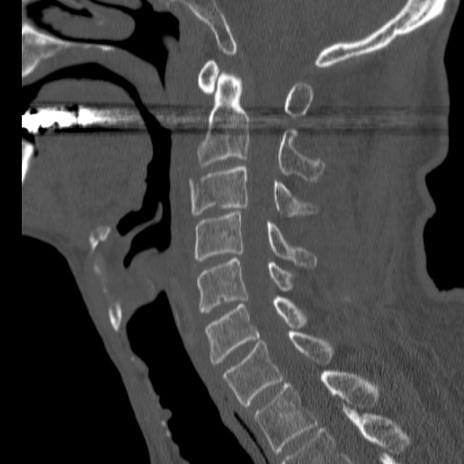

症例46 頚椎CT(矢状断像)

【症例】80歳代男性

【主訴】両側頚部〜上肢のしびれ

【現病歴】昨日、自宅内で転倒、その後より上記症状あり。意識障害なし。

【身体所見】両側上肢のallodynia(熱痛覚過敏)あり。MMTおよびDTRは正確な所見取れず。両上肢の挙上はなんとか可能。

異常所見と診断は?